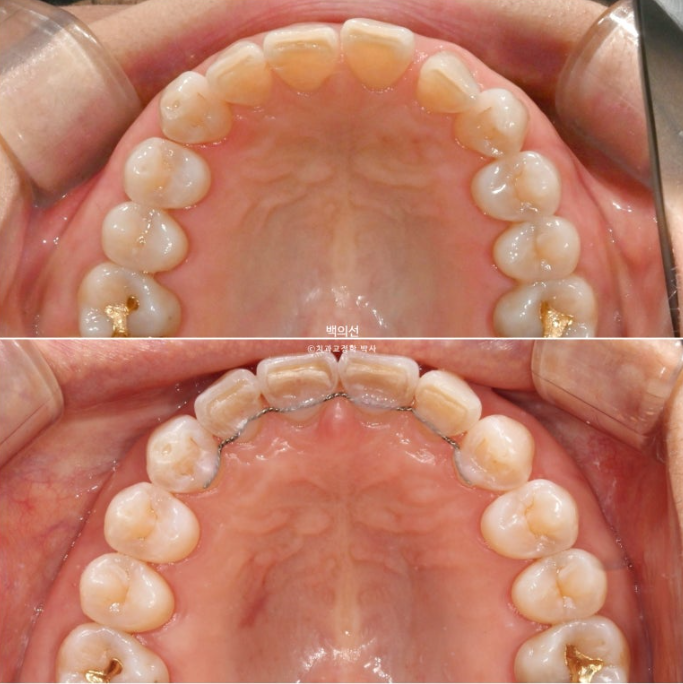

25.02

레진 치료를 감쪽같이 잘 해놓으셨습니다.

파란 화살표는 틈을 메워놓은 레진 입니다.

벌어진 틈을 메워놓는 레진을 제거한 모습입니다.

생각보다 틈이 꽤 크죠?

하지만 이 정도의 벌어짐, 틀어짐에는 인비절라인 익스프레스가 적절합니다.

25.08

25년 5월부터 7월까지 7개 추가장치를 모두 낀 후 치료를 마쳤습니다.

원래 좋았던 어금니 교합은 잘 유지가 되었씁니다.